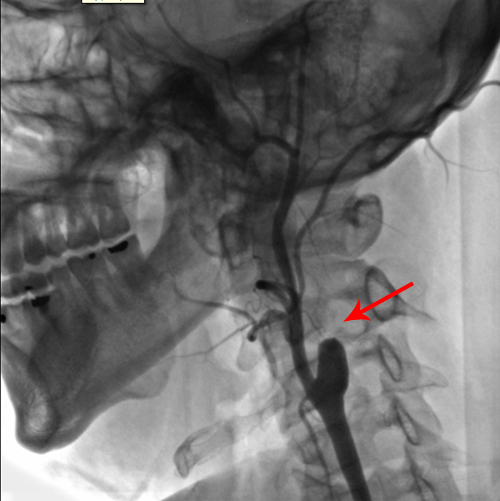

6月14日外院行全脑血管造影示左侧颈内A起始部闭塞,左侧后交通A开放,向左侧大脑前、大脑中A供血。

2011年7月3日和7月4日,协作组张勤奕教授分别为这两位患者实施了左侧颈内动脉残根切除术。